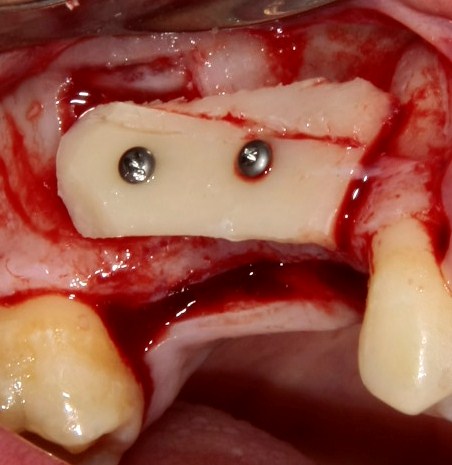

К установке имплантов можно приступать через 3-4 месяца (рис 52, 53):

Рисунок 52, 53. Установка импланта через 3 месяца после удаления зуба и синуслифтинга: слева – скелетирование верхней челюсти, справа – установленный имплантат.

При наличии соответствующих условий возможно проведение операции немедленной имплантации одновременно с синуслифтингом (рис 54, 55, 56):

Рисунок 54, 55, 56. Проведение операции синуслифтинга одномоментно с удалением зуба и установкой импланта.

В ходе воспалительного процесса, при излишне травматичном удалении или вследствие анатомических особенностей нередко отсутствует вестибулярная стенка лунки зуба – в дальнейшем, это может привести неблагоприятному эстетическому и функциональному результату. Костный фрагмент, получившийся при создании доступа в верхнечелюстную полость, можно использовать для пластики внешней стенки лунки (рис 57, 58, 59):

Рисунок 57, 58, 59. Пластика внешней стенки лунки костным фрагментом при немедленной имплантации и синуслифтинге: слева – этап синуслифтинга и имплантации, в центре – пластика внешней стенки альвеолярного отростка методом аутотрансплантации костного фрагмента, справа – этап установки формирователей десны через 3 месяца после имплантации.